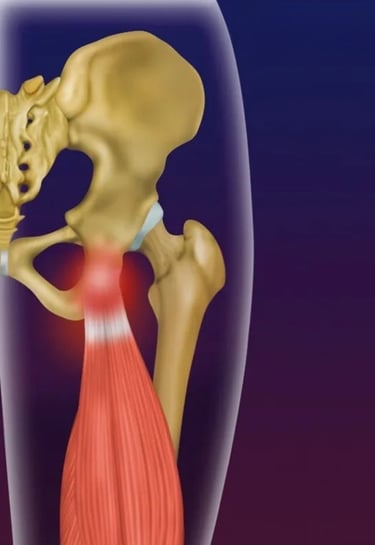

Osteonecrose da cabeça do fêmur

A Osteonecrose da cabeça do fêmur ocorre devido a um defeito na circulação sanguínea para a cabeça do fêmur, levando à morte do osso nessa região, fazendo com que o paciente tenha dor no quadril, muitas vezes acompanhada de dor na coxa.

Essa dor é pior aos movimentos ou ao fazer esforços físicos, muitas vezes limitando o paciente de andar médias distâncias.

Faz-se o diagnóstico com a Ressonância Magnética.

Já em casos avançados, realiza-se o tratamento com a cirurgia de prótese do quadril, na qual substitui-se a articulação com desgaste por uma articulação metálica, que irá reproduzir os movimentos e funções de um quadril normal.